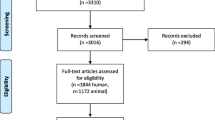

A total of 2414 records were identified through searches. 458 publications were excluded as duplicates. 167 articles were assessed by full-text review. 26 studies were included in qualitative synthesis and 6 studies were further included in the quantitative analyses. Figure 1 provides an overview of the study selection process for the systematic review (Fig. 1). Based on the results of the full-text analysis, following markers were evaluated: hepatocyte growth factor (HGF), vascular endothelial growth factor VEGF, interleukin-1 (IL-1), interleukin-6 (IL-6) and serum hyaluronate (HA). Quantitative analysis was possible for IL-6 and HA.